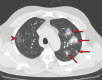

Chest CT has a potential role in the diagnosis, detection of complications, and prognostication of coronavirus disease 2019 (COVID-19). Implementation of appropriate precautionary safety measures, chest CT protocol optimization, and a standardized reporting system based on the pulmonary findings in this disease will enhance the clinical utility of chest CT. However, chest CT examinations may lead to both false-negative and false-positive results. Furthermore, the added value of chest CT in diagnostic decision making is dependent on several dynamic variables, most notably available resources (real-time reverse transcription-polymerase chain reaction [RT-PCR] tests, personal protective equipment, CT scanners, hospital and radiology personnel availability, and isolation room capacity) and the prevalence of both COVID-19 and other diseases with overlapping manifestations at chest CT. Chest CT is valuable to detect both alternative diagnoses and complications of COVID-19 (acute respiratory distress syndrome, pulmonary embolism, and heart failure), while its role for prognostication requires further investigation. The authors describe imaging and managing care of patients with COVID-19, with topics including (a) chest CT protocol, (b) chest CT findings of COVID-19 and its complications, (c) the diagnostic accuracy of chest CT and its role in diagnostic decision making and prognostication, and (d) reporting and communicating chest CT findings. The authors also review other specific topics, including the pathophysiology and clinical manifestations of COVID-19, the World Health Organization case definition, the value of performing RT-PCR tests, and the radiology department and personnel impact related to performing chest CT in COVID-19. ©RSNA, 2020.